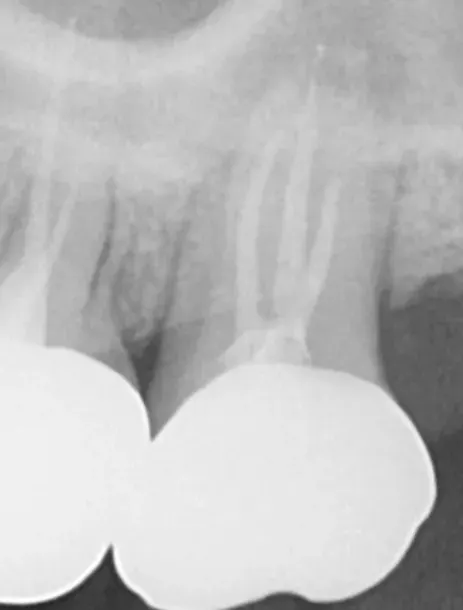

Precise diagnosis(radiography/pulp examination, etc.)

Cavity removal and infection management

Confirm pulp condition and determine viability of vital pulp therapy